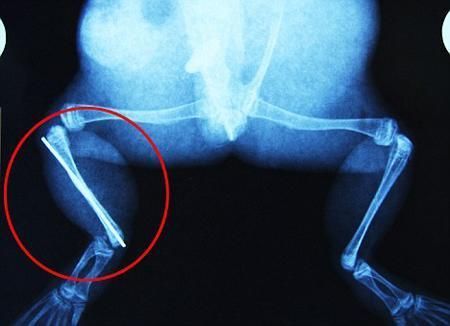

環(huán)球網(wǎng)4月2日?qǐng)?bào)道 據(jù)《每日郵報(bào)》報(bào)道,上個(gè)月,南非大牛蛙布魯萊的右小腿被鄰居家的一只狗咬到,導(dǎo)致粉碎性骨折,現(xiàn)在經(jīng)過(guò)2個(gè)小時(shí)的手術(shù),它的斷腿已經(jīng)被接上,它也因此成為有史以來(lái)第一只通過(guò)外科手術(shù)用鋼針接上斷腿的青蛙。

布魯萊的主人,居住在南非約翰內(nèi)斯堡附近的62歲的安妮·米恩斯說(shuō):“我對(duì)這只青蛙如此關(guān)心,人們一定認(rèn)為我瘋了,但是我無(wú)法眼睜睜看著它那么痛苦。青蛙因其靈活的腿腳而著稱(chēng),一想到布魯萊的腿里要留下一個(gè)薄金屬片,我就感到心痛。然而我知道,如果不進(jìn)行手術(shù),布魯萊以后就沒(méi)辦法動(dòng)彈了。因此我匆匆趕到獸醫(yī)那里,央求他給這只可憐的青蛙動(dòng)手術(shù)。這位獸醫(yī)整天救助小貓小狗,他很難理解為什么我這么擔(dān)心一只青蛙,但是最終他還是答應(yīng)了給布魯萊做手術(shù)。手術(shù)后是幾個(gè)小時(shí)的焦急等待,我們希望它能快快蘇醒過(guò)來(lái)。不過(guò)現(xiàn)在它的傷口已經(jīng)愈合,又能在花園里跳來(lái)跳去了。X光照射顯示,它會(huì)恢復(fù)的跟以前一樣。”

野生生物專(zhuān)家安妮經(jīng)常為學(xué)校寫(xiě)教材,她認(rèn)為這是人類(lèi)第一次通過(guò)手術(shù)給一只青蛙接斷腿。在手術(shù)開(kāi)始階段,獸醫(yī)把少量給狗用的麻醉藥注入到這只青蛙體內(nèi),讓它失去知覺(jué)。然后他在布魯萊的斷腿上切開(kāi)一個(gè)小口,把一根小鋼針植入腿里。最后獸醫(yī)給它縫了9針,把切口縫合在一起。僅僅幾周后,布魯萊就能在安妮家附近活動(dòng)了。這只青蛙大約已有25歲,主要以嚙齒動(dòng)物、蛇和其他青蛙為食。布魯萊所屬的牛蛙種群正在不斷減小,目前只能在非洲南部的濕地里才能看到這種青蛙。